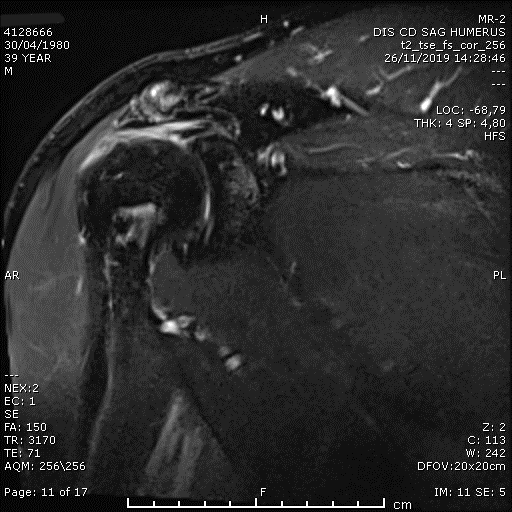

Artroskopi Yardımlı Latissimus Dorsi Tendon Transferi (LDTT)

Masif onarılamaz rotator manşet yırtıklarında (MIRCT) uygulanan latissimus dorsi tendon transferi tekniği. Sırt kasının tendonu omuz bölgesine transfer edilerek kaybedilen omuz fonksiyonu yeniden kazandırılmaktadır.

Preoperatif omuz MRI

Masif Rotator Manşet Yırtığı — Açık Komplet Tamir (OCR)

Masif onarılamaz rotator manşet yırtıklarında açık cerrahi ile tam tamir tekniği. Ameliyat öncesi ve sonrası MRI görüntüleri ile tamir başarısı izlenmektedir.

Preoperatif omuz MRI — masif yırtık